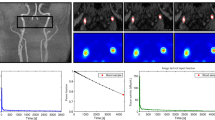

Values for kinetic parameters, SUVmax and T/N ratio, MR imaging and CD34 scores, Ki-67 index and ENT1 mRNA levels are given in Table 1. First, there was a good correlation between the T/N ratio for [18F]-FLT and the Ki-67 index, a measure of proliferation (r = 0.733, p = 0.0002; Fig. 2a). To understand the basis of the increased T/N ratio, we examined the relationship between the composite K i with T/N and found good correlation (i = 0.61, p = 0.0034; Fig. 2b). Changes in K i may reflect changes in K 1 (influx across the BBB) and k 3 (phosphorylation of [18F]-FLT). There was good correlation between K 1 and T/N ratio (r = 0.8042, p < 0.0001; Fig. 2c). There was no significant correlation between k 3 and T/N ratio (Fig. 2d).

Linear regression analysis between T/N ratio [18F]-fluorothymidine ([18F]-FLT) and the Ki-67 index, a measure of proliferation, and the [18F]-FLT positron emission tomography (PET) kinetic parameters (K 1, k 3 and K i ). a There was a significant correlation between T/N ratio and Ki-67 index (r = 0.733, p = 0.0002 ). b There was a correlation between T/N ratio and K i (r = 0.61, p = 0.0034) and c K 1 (r = 0.8042, p < 0.0001), d but not k 3

Next, BBB disruption may cause an increase in K 1 and thus K i . Indeed K 1 and K i were both significantly correlated with BBB disruption (Gd-enhancement score) (p = 0.0004, Fig. 3a; p = 0.0032; Fig. 3b). In addition, BBB disruption correlated with both T/N ratio and Ki-67 proliferative index (p = 0.0111, Fig. 3c; p = 0.0024, Fig. 3d). The Gd-enhancement score also showed significant correlations with ENT1 mRNA levels and CD34 scores (p = 0.016, Fig. 3e; p = 0.007, Fig. 3f).

Correlation the blood–brain barrier (BBB) breakdown in tumors [gadolinium (Gd) enhancement score] with kinetic parameter (K 1 and K i ), T/N ratio, Ki-67, equilibrative nucleoside transporter 1 (ENT1) [real-time polymerase chain reaction (RT-PCR)], and CD34 score using the nonparametric Spearman’s rank test. There was a significant correlation of the Gd-enhancement score with a K 1 (p = 0.0004), b K i (p = 0.0032,), c T/N ratio (p = 0.0111,), d Ki-67 index (p = 0.0024), e ENT1 (RT-PCR) (p = 0.016), and f CD34 score (p = 0.007)

Finally, in contrast to the correlation of K 1 and K i with BBB disruption, there was no significant correlation of these two parameters with ENT1 mRNA levels (Fig. 4a, b), although there was a significant relationship between ENT1 and k 3 (r = 0.4778, p = 0.0285, Fig. 4c). There was also no significant correlation of the CD34 score and either K 1, K i or k 3 (Fig. 5a–c).

Linear regression analysis between equilibrative nucleoside transporter 1 (ENT1) messenger RNA (mRNA) expression by real-time polymerase chain reaction (RT-PCR) and the [18F]-fluorothymidine ([18F]-FLT) positron emission tomography (PET) kinetic parameters (K 1, K i and k 3). There was no correlation between a K 1 and b K i , but c there was a correlation between ENT1 (RT-PCR) and k 3 (p = 0.0285